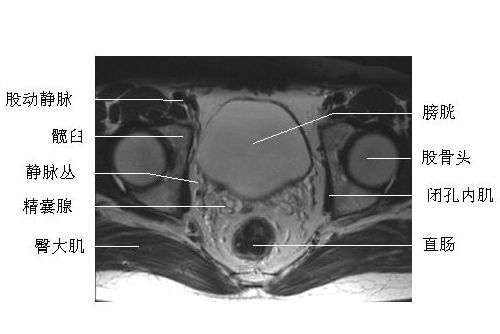

男性盆腔横断面-MRI图片

男性盆腔横断面-MRI图